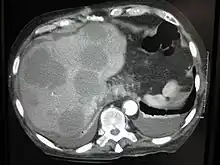

Initially, nearby lymph nodes are struck early.[10] The lungs, liver, brain, and bones are the most common metastasis locations from solid tumors.[10]

- Liver metastasis: hepatomegaly (enlarged liver), nausea[10] and jaundice[10]

Metastatic tumors are very common in the late stages of cancer. The spread of metastasis may occur via the blood or the lymphatics or through both routes. The most common sites of metastases are the lungs, liver, brain, and the bones[10]